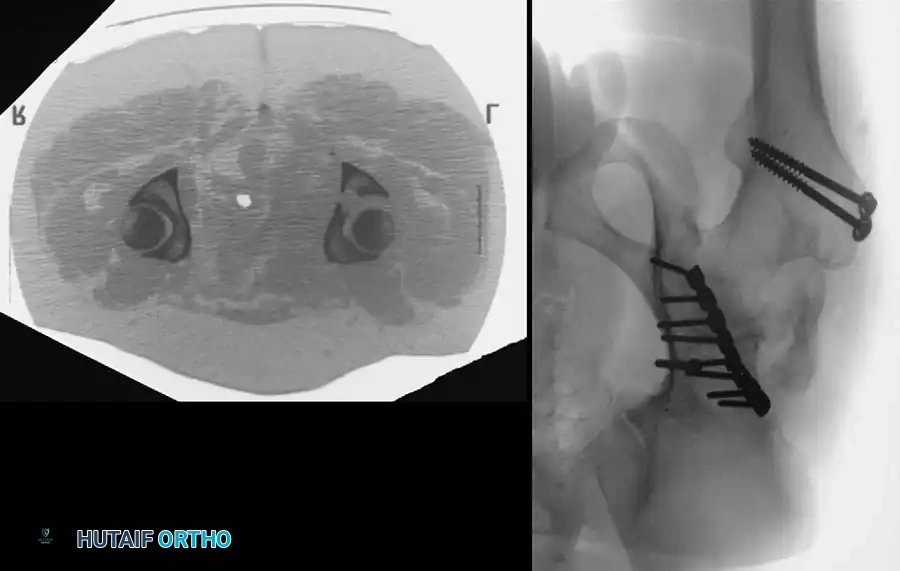

Fig. 53-4 Anteroposterior pelvic radiograph ( A ) and CT scan ( B ) of irreducible hip dislocation with posterior wall acetabular fracture. Posterior wall fragment is incarcerated, blocking reduction.

If closed reduction under conscious sedation or general anesthesia fails, urgent open reduction is mandated. A rapid, fine-cut (2-3 mm) Computed Tomography (CT) scan should be obtained to identify the incarcerating fragment—often a rotated posterior wall fragment or an intra-articular osteochondral loose body. Prolonged dislocation exponentially increases the risk of femoral head osteonecrosis and irreversible sciatic nerve ischemia.

Advanced Imaging: Computed Tomography (CT)

While plain radiographs provide the foundation for classification, fine-cut CT scanning with 2D multiplanar and 3D surface-rendered reconstructions is the gold standard for modern surgical planning.

CT imaging excels at identifying:

* Intra-articular osteochondral fragments (loose bodies).

* Marginal impaction of the articular cartilage.

* The exact size and comminution of posterior wall fragments.

* The orientation of fracture lines to plan optimal screw trajectories.

Associated Surgical & Radiographic Imaging

Hutaifortho's Orthopaedic Diagram